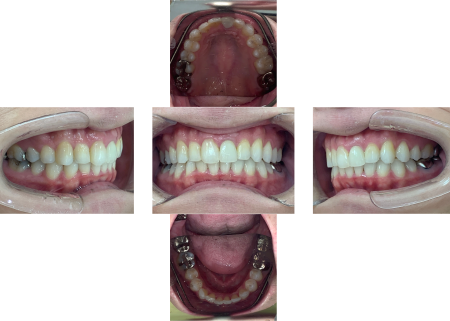

歯がきれいに並び、舌が動かしやすくなり発音もよくなりました。

患者様からは「見た目がよくなっただけでなく、発音も改善できてうれしい」とご満足いただけました。

後戻りもなく、現在も定期検診にご通院されています。